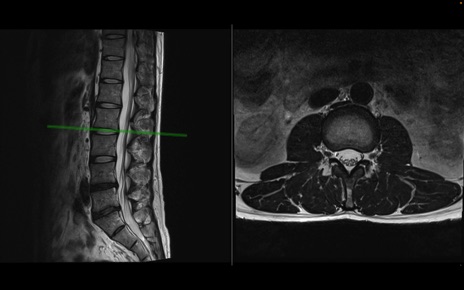

【整形】TIPS症例1 腰椎MRI 横断像と矢状断像

【症例】40歳代男性

【主訴】左臀部〜大腿後面痛み

【現病歴】2週間前から腰痛あり。2日前に夜中にくしゃみをした際に激痛が出現。疼痛強いため来院。

【身体所見】左臀部〜大腿後面、下腿後面のしびれ。SLR -/+ 30度、うつ伏せ困難、筋力低下なし。

異常所見と診断は?